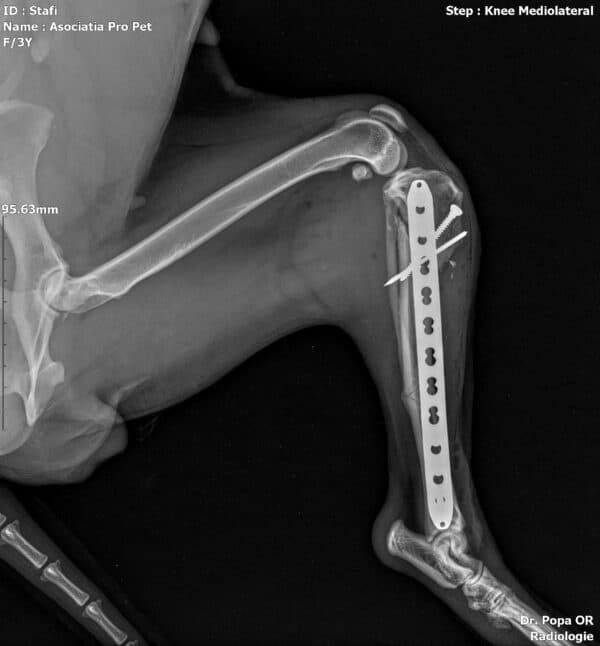

Jubina im Vet-House ist operiert, total menschenbezogen und verschmust und sehr sehr dünn. Wenn sie da raus muss, hat sie sicher wenig Chancen..

Röntgenbilder nach OP zugefügt.

JUBINA wurde angefahren und hat einen gebrochenen Hinterlauf, der zeitnah operiert wird (10/2022).

Beinbruch nach Autounfall, wurde operiert, aktuell viel zu dünn (10/22)